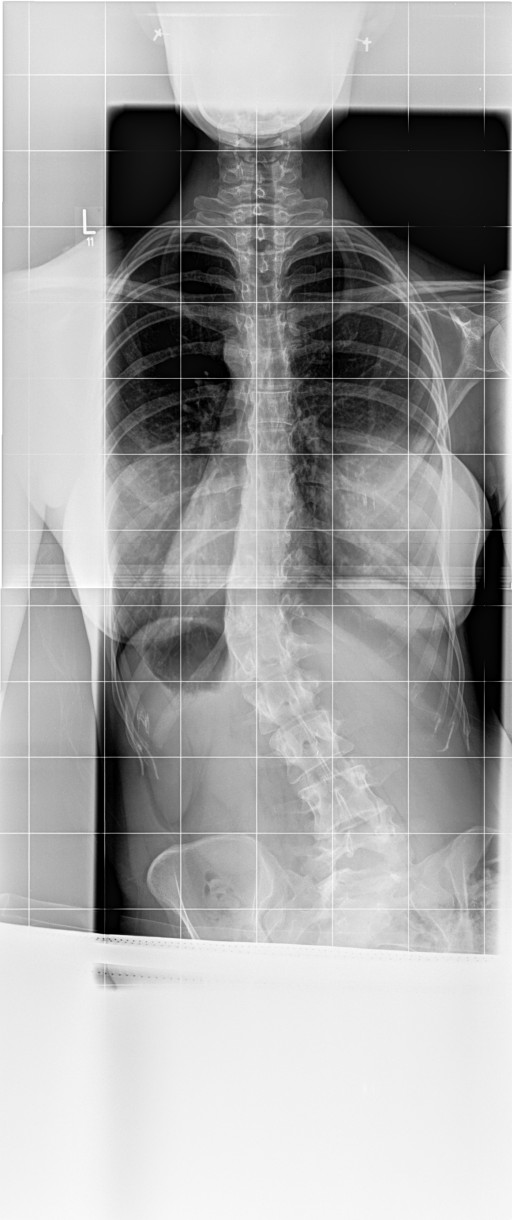

Bei mir steht der Brustknochen, bzw das Sternum total hervor ( siehe Bild , Datei ) In der Werner Wicker Klinik, sowie in Neustadt sagte man mir der vorstehende Brustknochen bzw das Sternum hätte nichts mit der Skoliose zu tun ?!? Aber die Wirbelsäule ist doch in sich verdreht, also hat es eigentlich doch etwas damit zu tun oder ? Vor 10 Jahren hatte ich diesen extremen Knochen nämlich noch nicht. Weis darüber jemand etwas ?

7.jpg

Aufnahme Herbst 2017

6.jpg

Sternum das immer weiter raus ragt